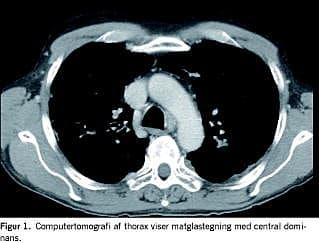

I. En 59-årig mand, der havde haft rektosigmoiditis siden 1981, fik opblussen under vedligeholdelsesbehandling med azathioprin og mesalazin. Behandling med højdosis steroid kompliceredes af aseptisk knoglenekrose og måtte seponeres. Patienten ønskede ikke operation, og derfor påbegyndtes behandling med infliximab med god effekt på hans tarmsymptomer. Der forelå negativ interferon-γ-test for tuberkulose (TB). Efter anden kur blev han træt og fik dyspnø, hovedpine, høj feber og forhøjet C-reaktivt protein. En røntgenundersøgelse af thorax viste et lille infiltrat. Luftvejssekret blev undersøgt for almindelige luftvejspatogener, legionella, pneumocyster samt TB og blod blev undersøgt med Cytomegalovirus (CMV)-polymerasekædereaktion (PCR) og Aspergillus galactomannan-antigentest. Patienten påbegyndte behandling med penicillin og clarithromycin uden effekt. På grund af tiltagende luftvejssymptomer og hypoksi med saturationsfald til 80% under korte gåture skiftede han til peroral sulfamethoxazol/trimethoprim og samtidig steroidkur. En computertomografi af thorax viste matglastegning (Figur 1). I trakealsekret og bronkial alveolær lavage fandt man ved PCR-undersøgelse P. jiroveci. Alle øvrige mikrobiologiske undersøgelser var negative. Patienten responderede godt på sulfamethoxazol/trimethoprim. Han fik dog pancytopeni i slutningen af kuren, hvorfor sulfamethoxazol/trimethoprim blev midlertidigt pauseret med god effekt. Patienten blev efterfølgende kolektomeret, og immunsuppressiv behandling kunne seponeres. Tre måneder senere afsluttedes den profylaktiske sulfamethoxazol/trimethoprimbehandling.

Taksigelse: Rene Jensen og Stanislaw Wasilewski, Billeddiagnostisk Afdeling, Regionshospitalet Viborg, takkes for hjælp til Figur 1.